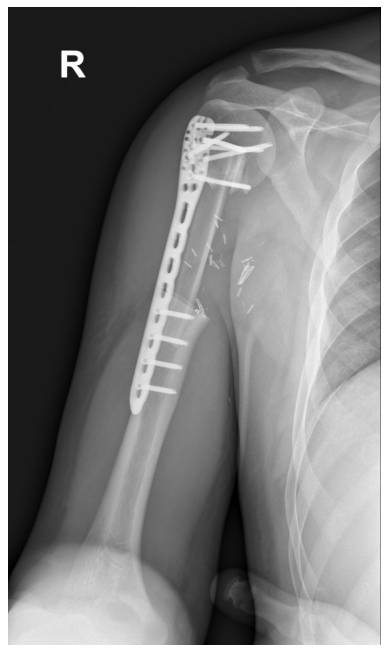

Ameliyat Sonrası: Röntgende rezeksiyon sonrası uygulanan vaskülerize fibulanın anatomik plak ile fikse edilmesi görülmekte